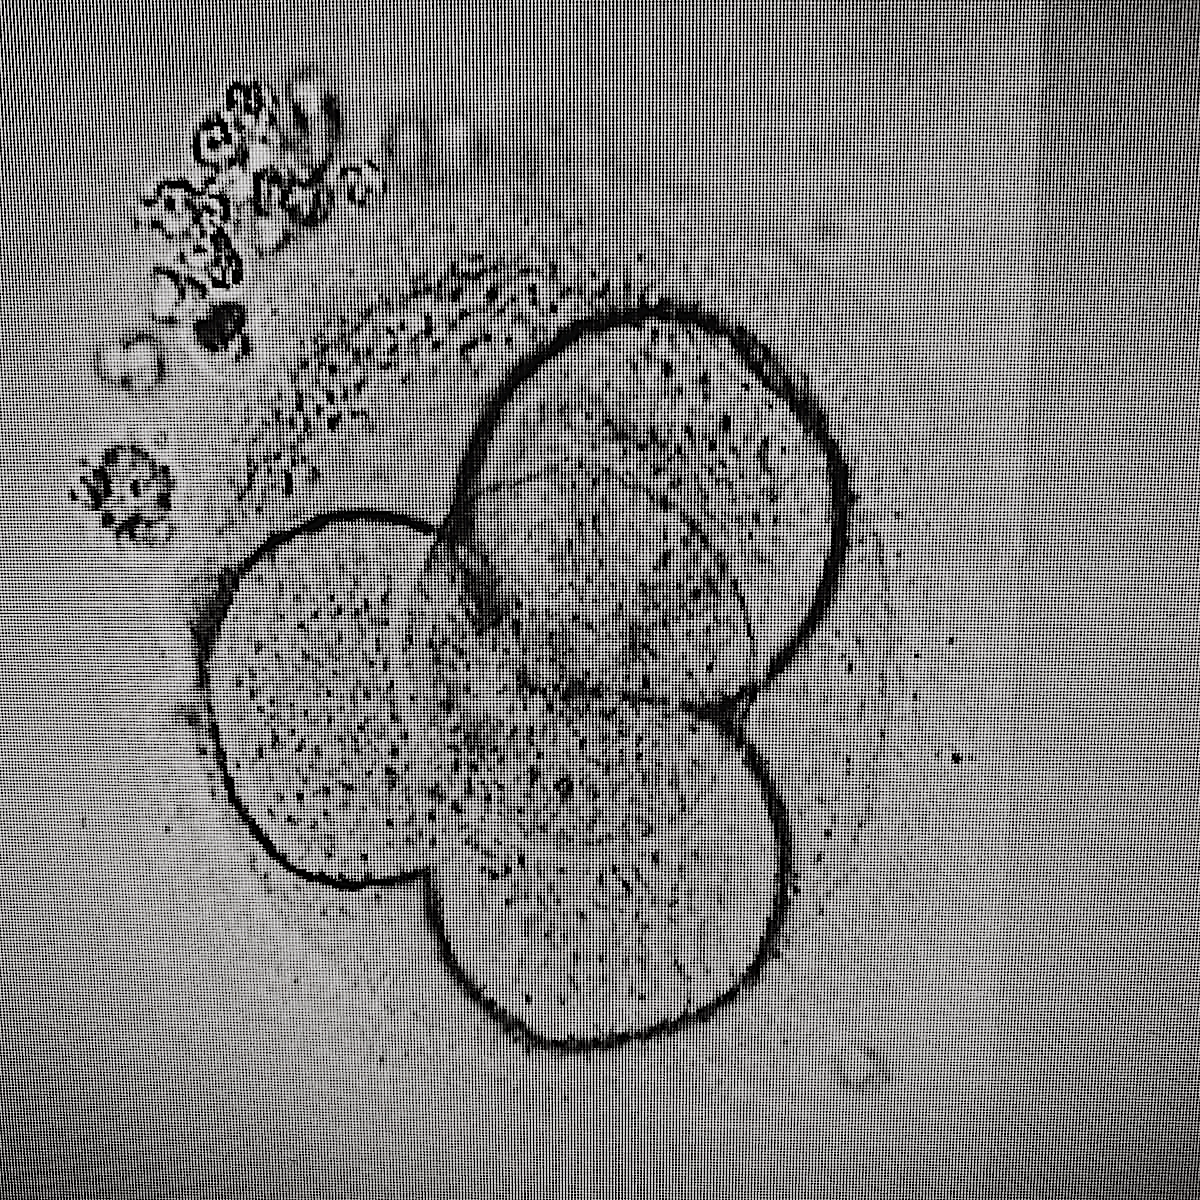

Фото ембріонів на 2 добу розвитку

Ембріони in vitro розвиваються в поживних середовищах до п'ятих - шостих діб в інкубаторах зі збереженням оптимальних умов (стабільний температурний режим, рівень вуглекислоти, кисню). Оцінка якості розвитку ембріонів ведеться за допомогою світлового мікроскопа. Ембріони високої якості на другу добу мають чотири клітини, на треті - вісім, на четверті - кількість клітин подвоюється, кордони між клітинами зливаються, а ембріон стає компактним, утворюється морула, на п'яту добу кількість клітин збільшується, починає формуватися бластоциста.